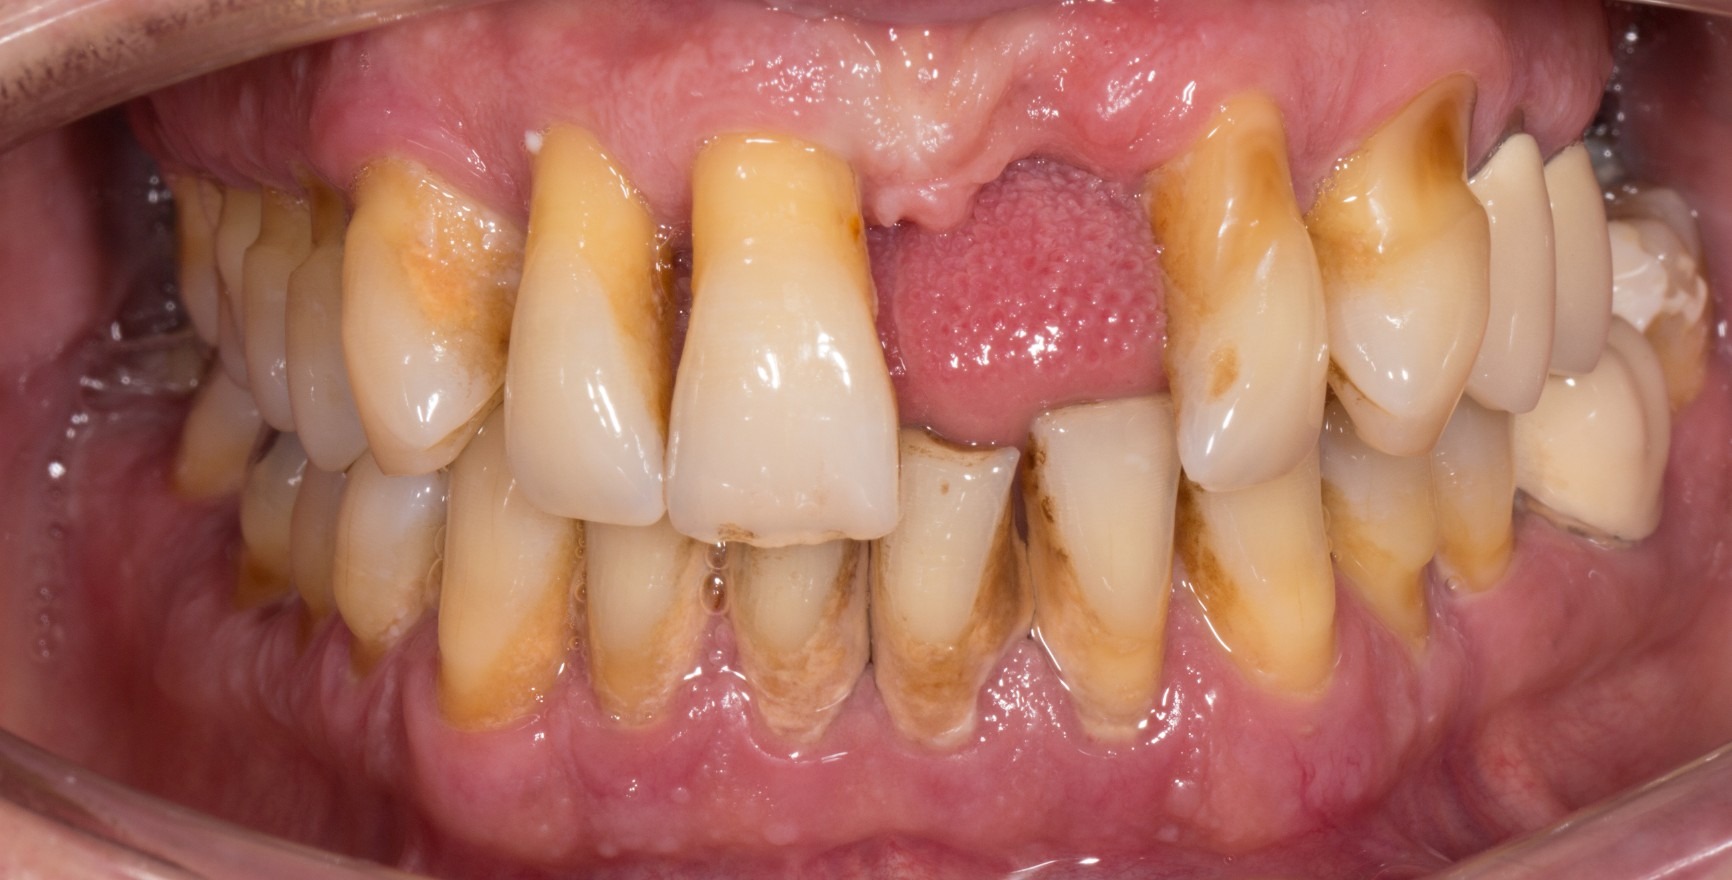

On distingue l'état de santé parodontale clinique d'un parodonte intact de celui d'un parodonte réduit déjà affecté par une perte d'attache clinique. Cette perte d'attache peut se produire :

à la suite d'une l'inflammation au cours d'une parodontite. La santé parodontale clinique décrit alors un état stable après l'achèvement réussi du traitement parodontal.

à la suite d'une récession

de manière iatrogène, par exemple à la suite d'un allongement chirurgical de la couronne (Chapple et al., 2018).

Le critère clinique est toujours l'absence de saignement lors d'un sondage minutieux (saignement au sondage = BoP). Une distinction est faite entre un diagnostic spécifique au site/à la dent avec un résultat BoP négatif au site de mesure correspondant, et un diagnostic au niveau de la dent ou du patient, pour lequel une valeur seuil d'un BoP ≤ 10 % répond toujours aux critères de santé parodontale clinique. La profondeur de sondage des poches ne doit pas dépasser 3 mm. Dans un parodonte réduit après un traitement parodontal, une valeur seuil de 4 mm est encore considérée comme un état stable (Matuliene et al., 2008).